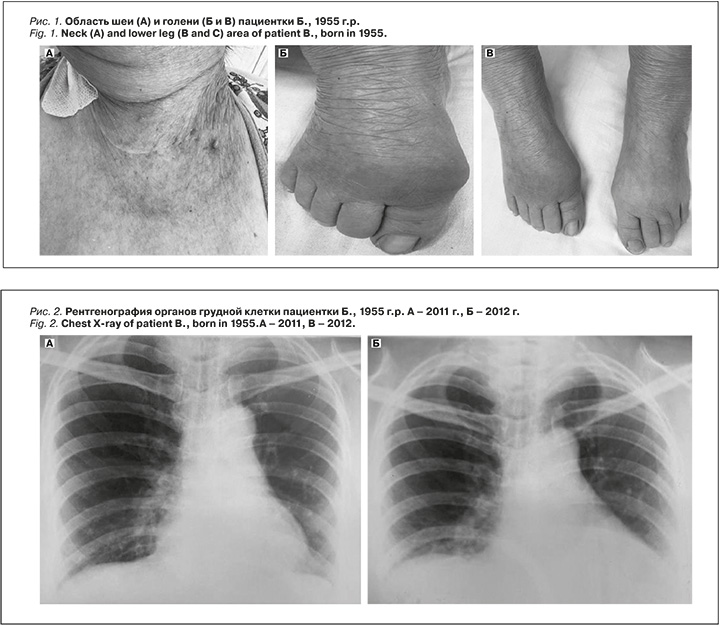

Объективный статус. Кожа и видимые слизистые оболочки сухие, желтушного оттенка. На передней поверхности шеи – послеоперационные рубцы после субтотальной резекции ЩЖ (рис. 1А). Отмечаются симметричные плотные отеки лица, голеней и стоп, а также гиперемия и припухлость кожи в области большого пальца правой стопы (рис. 1Б и 1В). Кожа на ощупь холодная, температура тела – 35,2 °C. Рост – 160 см, масса тела – 68 кг, индекс массы тела – 26,6 кг/м². Сатурация кислорода на атмосферном воздухе – 70–72%. Зев не гиперемирован, миндалины не увеличены. Частота дыхательных движений – 15 в минуту, дыхание в нижних отделах легких не проводится, хрипов нет. Тоны сердца ослаблены, ритм правильный, частота сердечных сокращений – 64 уд/мин. Артериальное давление – 60–50/40 мм рт.ст. Живот увеличен за счет выраженного подкожно-жирового слоя, мягкий, безболезненный при пальпации. Печень пальпируется по краю правой реберной дуги, селезенка не определяется. В поясничной области – без видимых изменений, симптом поколачивания по XII ребру не исследован. Ректальная температура – 32,1 °C.

Анамнез заболевания. 21.04.2006 пациентке была выполнена субтотальная резекция ЩЖ по поводу опухолевидного образования. При гистологическом исследовании ткани ЩЖ верифицирована пролимфоцитарная лимфосаркома (40210-4, 40215-9, 141307-8). Проведено более пяти курсов химио- и лучевой терапии. В течение трех последующих лет наблюдался малопродуктивный кашель, в связи с чем пациентке ежеквартально выполнялась рентгенография органов грудной клетки (рис. 2). По данным рентгенограммы: слабо выраженные экссудативные очаги в нижней доле правого легкого, корни легких мало структурные, тень сердца расширена, аорта уплотнена. С 2007 г. появились жалобы на дисфагию и дисфонию. С 2011 г. стал беспокоить суставной синдром, по поводу которого пациентка периодически принимала нестероидные противовоспалительные средства.